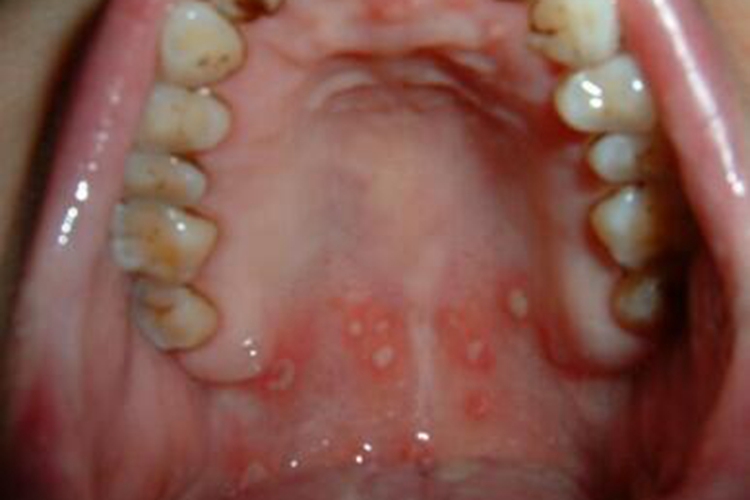

二期口腔梅毒主要发生于口腔,临床可表现为局部黏膜表面出现红斑,散在分布,边界较清,呈圆形或不规则形,直径约1cm,部分表面覆盖灰白色假膜,周围有红晕,无明显疼痛。